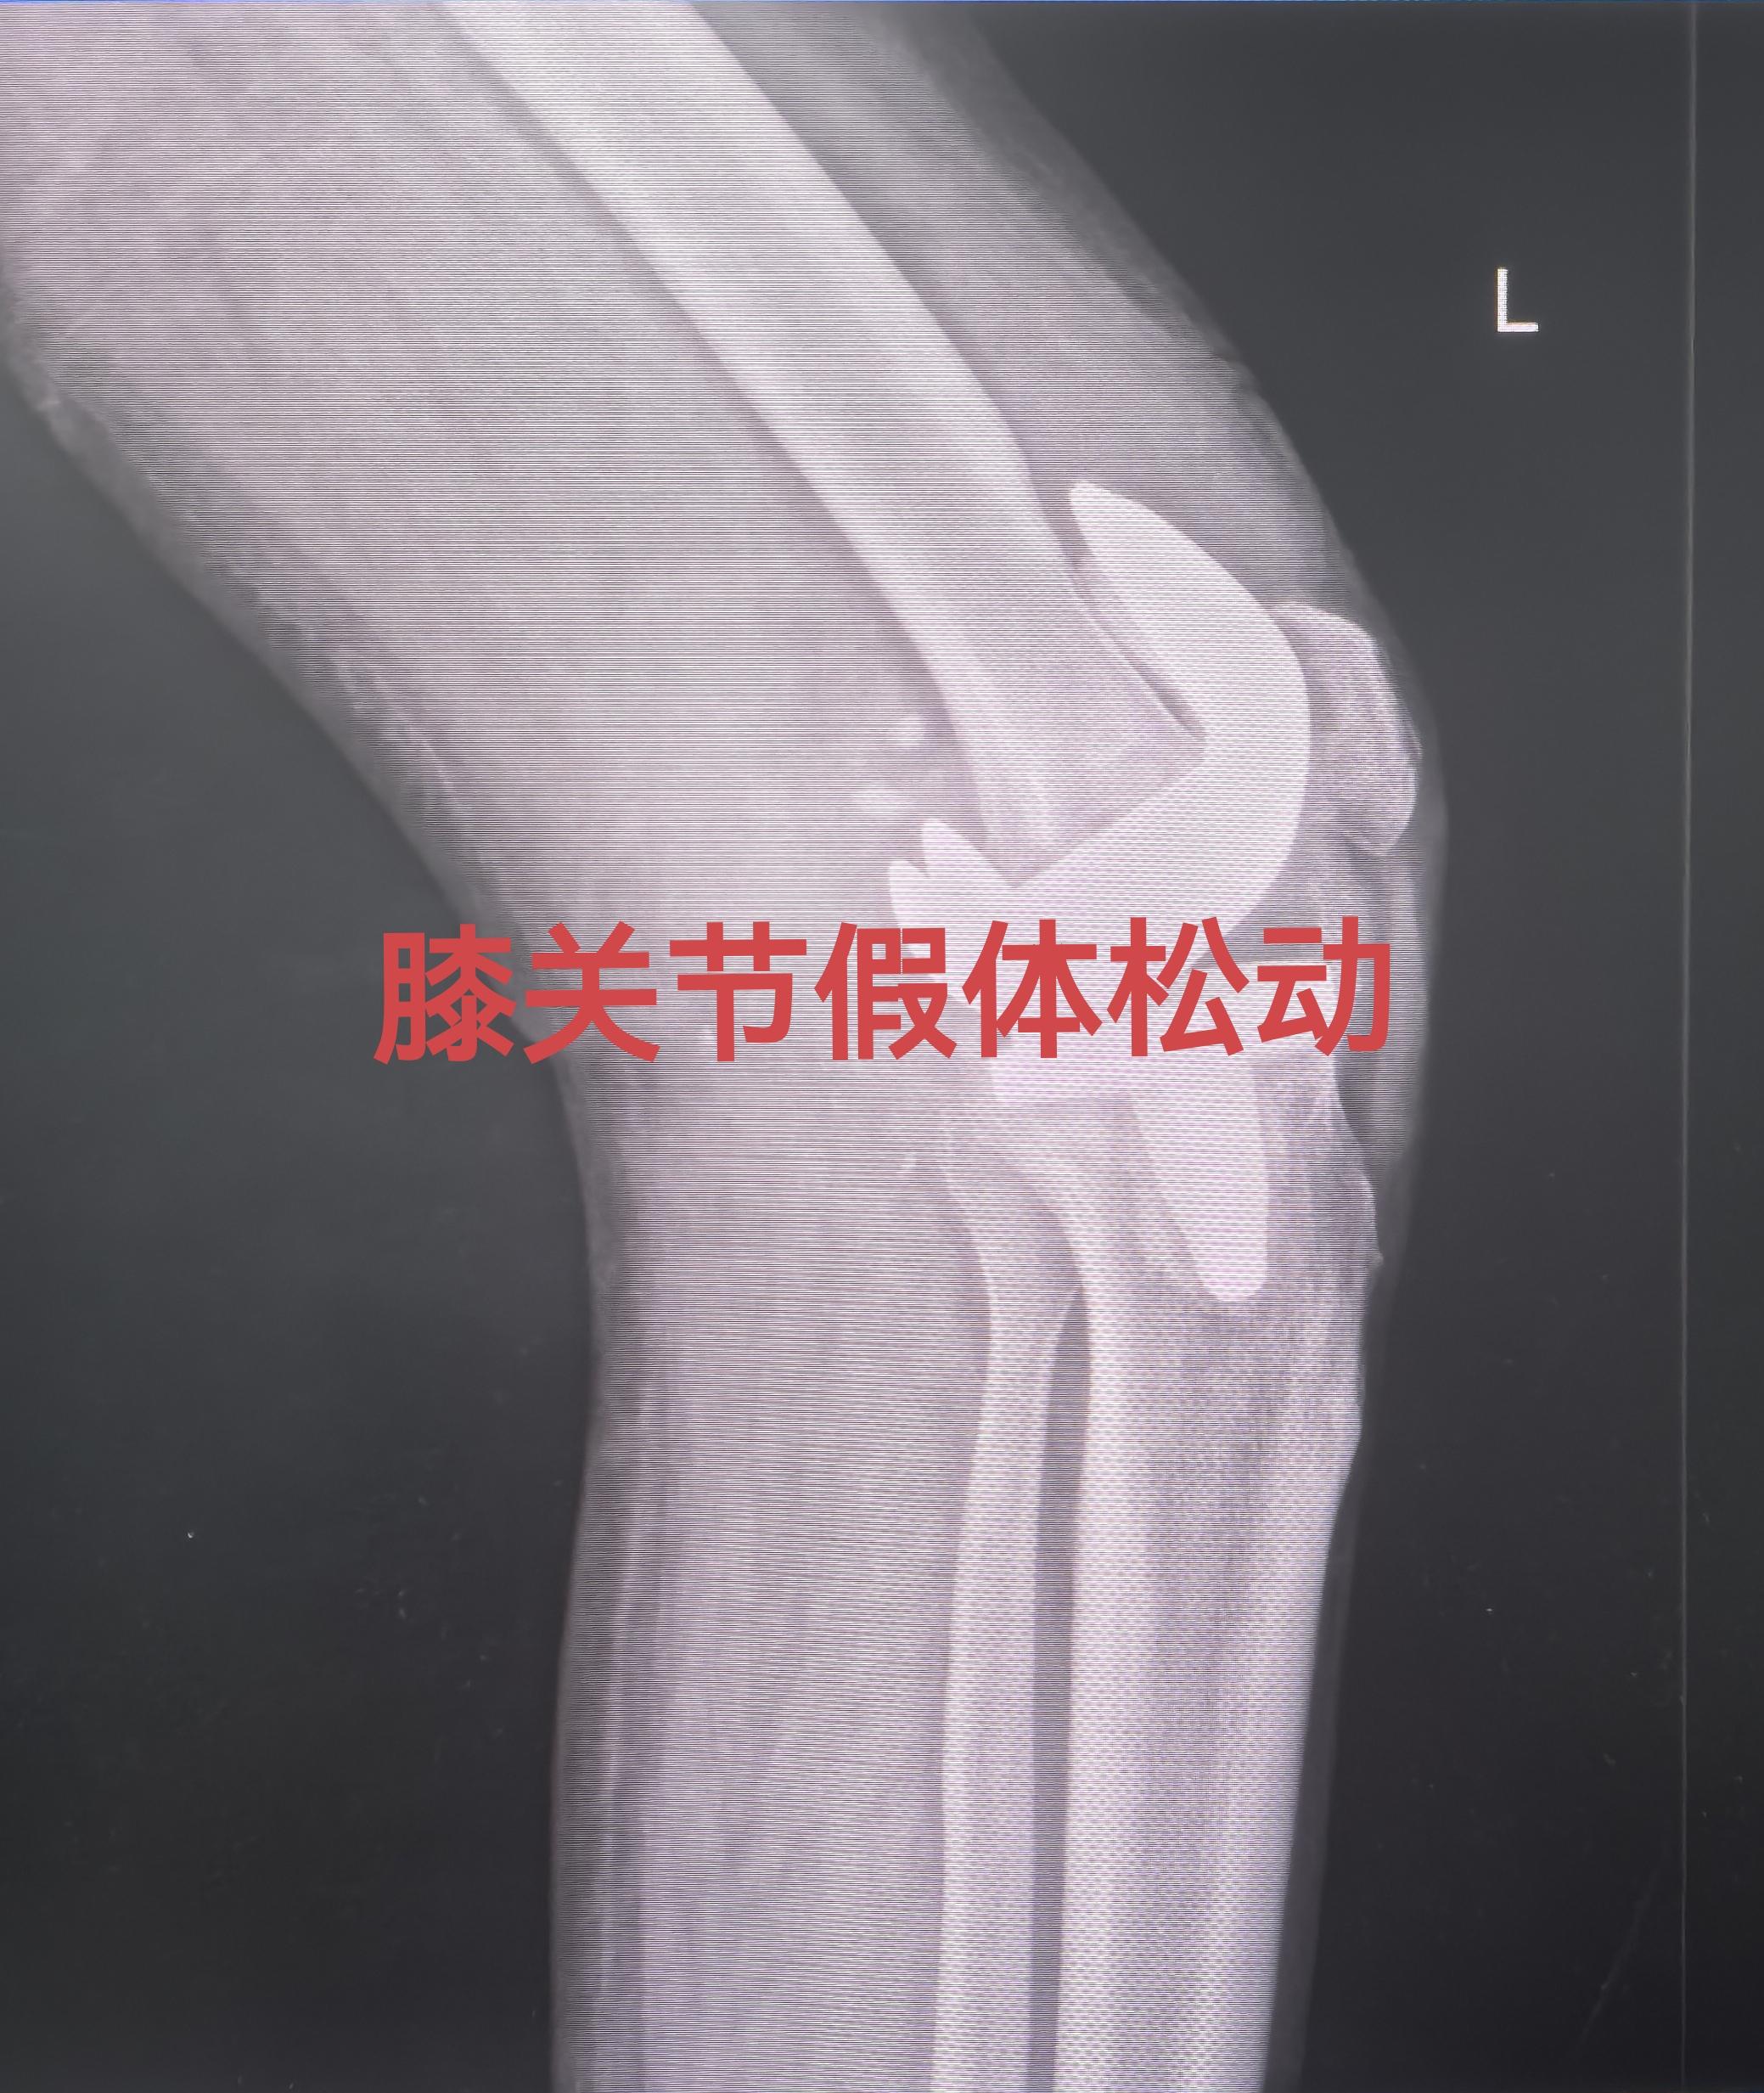

膝关节翻修。80岁老爷子,膝关节置换术后假体松动,一期翻修,再次续命20年🌹